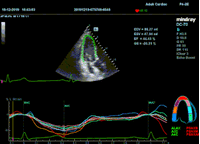

Всё изменилось с появлением технологии Speckle-tracking. Ультразвуковые приборы компании Mindray DC 8, 70, 80, Resona 6,7 оснащены данной функцией. Для использования необходим ЭКГ-канал. В чем же смысл данного технологического новшества? Прибор использует видео петли сечений миокарда, разбивает миокард на точки со стабильной визуализацией – speckle, и затем производит слежение каждой точки в течении нескольких сердечных циклов. Изменение пространства между точками дает нам представление о возможностях деформации миокарда, как продольной – Longitudinal Strain, так и деформации скручивания – торсии и Radial Strain.

На сегодняшний день в мировой клинической практике используется продольный Strain. Методика позволяет выявить нарушения в работе миокарда в каждом отдельном сегменте в среднем до 5 лет раньше клинического манифеста. Так же есть возможность оценки и диастолической функции, с гораздо более высокой чувствительностью чем тканевой допплер. Возможности радиального стрейна изучаются, за этой методикой будущее.

Как работать с данным методом? Для Longitudinal Strain необходимо записать видео петли апикальных сечений в память прибора: 4С, 3С, 2С. Для повышения качества трекинга рекомендуется производить запись на выдохе пациента. Затем произвести разметку по линии эпикарда, перикарда и центра миокарда. Нажатием кнопки «начать слежение» активируется программный алгоритм, видео петля оживает вместе с размеченными точками-speckle’ами. При необходимости производится коррекция. После анализа всех трех сечений можно получить данных продольной деформации как в среднем значении, так и по каждому сегменту миокарда левого желудочка. Нормальным показателем считается Longitudinal Strain -20%. Нижней границей -14%.

Видео примеры на приборе Mindray DC 70